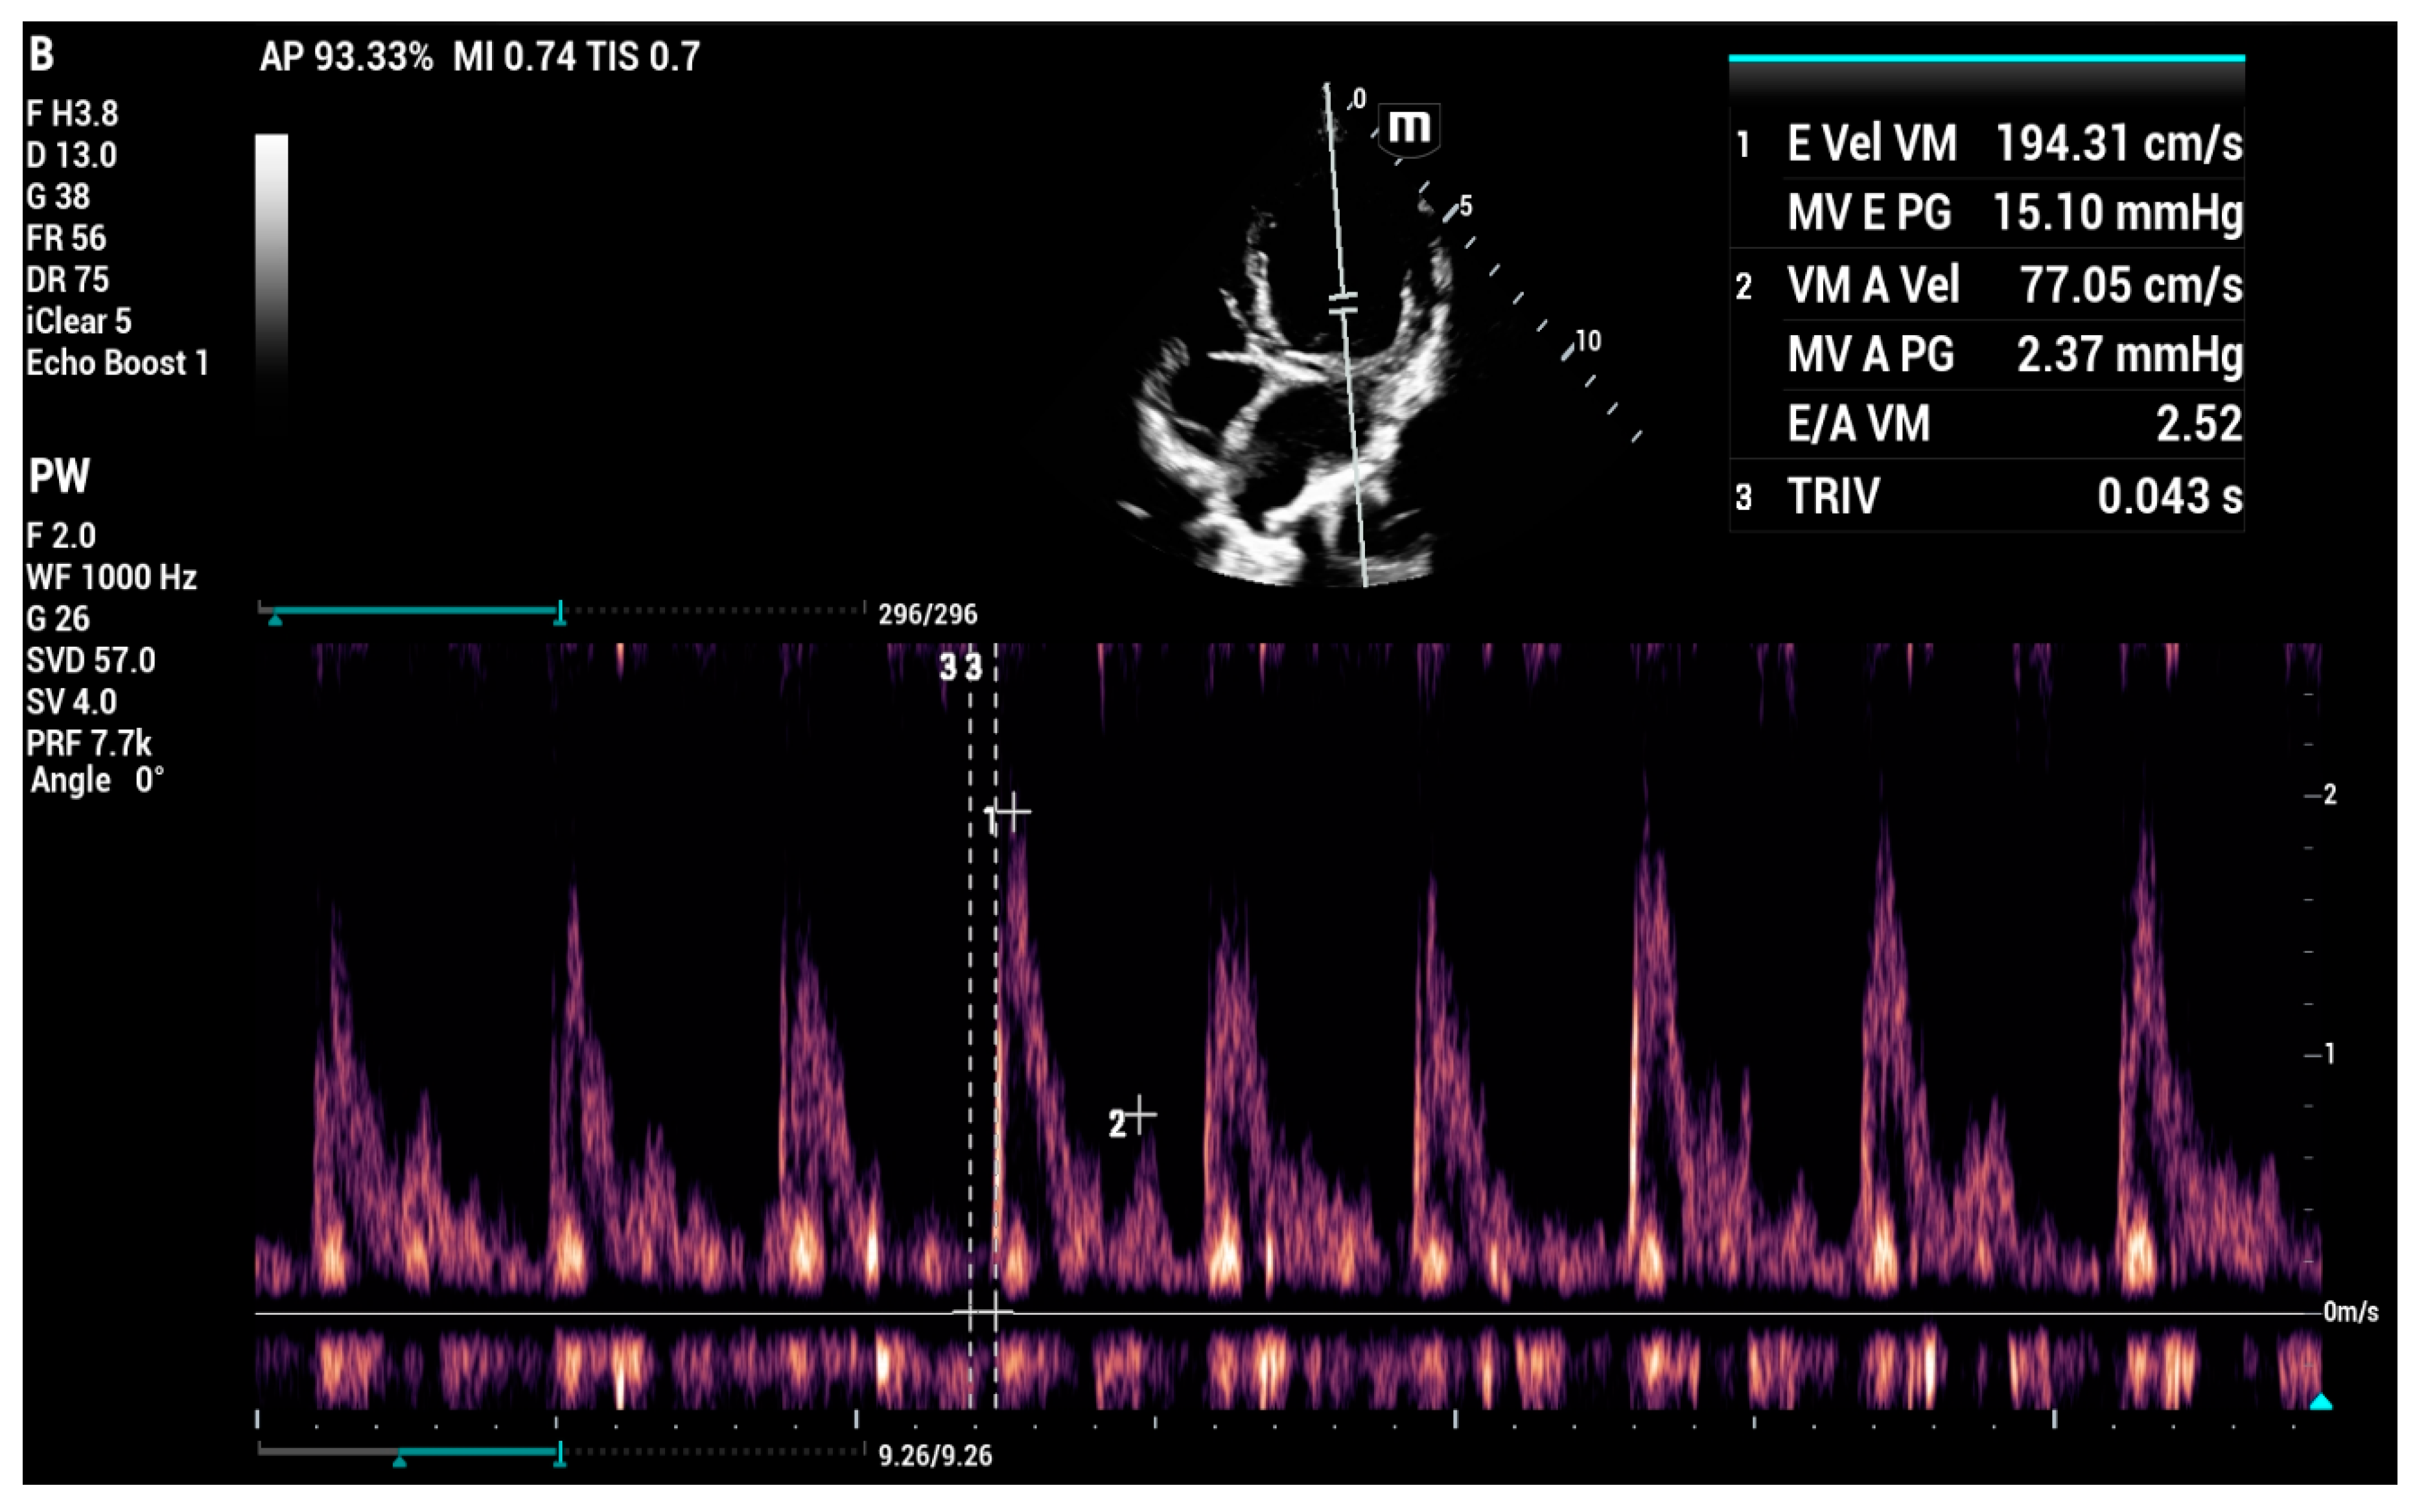

4.8.5. Vmax Wave E

4.8.6. E-Wave Deceleration Time

4.8.7. E/IVRT Ratio

4.8.8. E/é Ratio of the Mitral Annulus